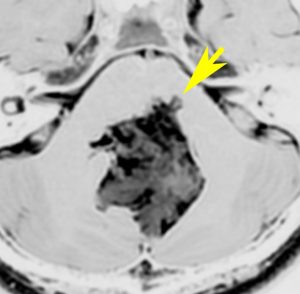

なぜ脳幹部からの無理な剥離が必要な手術を勧めるか

30歳くらいの時に初回の開頭手術で部分摘出を受けて,現在70代の患者さんの画像です。黄色は今も残っている腫瘍です。2度目の開頭手術,3度目の開頭手術では癒着で脳幹部や脳神経からの剥離が全くできませんでした。現在でも脳幹部に入り込むように腫瘍がゆっくり大きくなっていて,体幹失調のために車椅子生活です。顔面神経麻痺,嚥下障害,構語障害,眼球運動障害などもあります。髄液吸収障害による水頭症を併発してシャント手術も受けています。

この患者さんの40年の経過はいろいろなことを教えてくれます。似たような患者さんをたくさん見てくると,初回手術で取りきれなかった類表皮のう胞を,2度目の開頭手術で完全摘出することはとても難しいという経験を積みます。

数十年後のことを考えるのであれば,初回手術で完全摘出するべきです